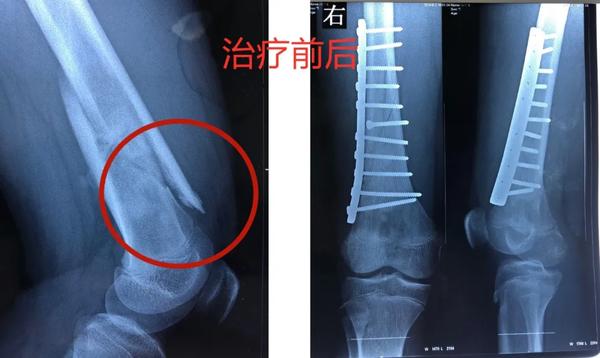

12岁的男孩儿浩浩,在学校上体育课,扭伤后突发右侧大腿剧烈疼痛,不能活动,被家人紧急送到医院,当地医院拍片后提示右股骨中下段斜行骨折。随后,医院按照一般骨折处理。

当地医生将病理组织送河南省肿瘤医院病理会诊,提示为骨肉瘤。消息犹如晴天霹雳,但更让两个孩子的父母痛苦的是,“由于按一般骨折做了手术、打了钢板和钢钉,破坏了肿瘤外面原本相对完整的包膜,这个自然屏障一旦被破坏,肿瘤细胞就会‘污染’周围组织,以后想再切干净就更困难了。”河南省肿瘤医院骨与软组织科主任、主任医师姚伟涛表示。

身体异常:排除感冒、发烧引起的,患者出现持续发热,并伴有体重下降,活动能力下降,且有难以解释的持续性疼痛。骨折:肿瘤持续“破坏蚕食”骨质,最后就像浩浩和晨晨一样,轻微的外力下就会发生一处甚至多处骨折。揪出骨肉瘤 核磁是关键那怎么才能确诊骨肉瘤呢?检查骨肉瘤首先要拍X片,其次是磁共振,最终要依靠活组织检查来确诊。一定不能忽视磁共振检查。王鑫提醒道:骨肉瘤就像一个表面看起来很小的水坑,实际上坑里的水已经向周围浸润了很大一片。在X光片上仅能看到很小的一个病灶,而在磁共振上,可以判断肿瘤的实际大小和确切范围,减少误诊漏诊。就像浩浩、晨晨这样,以为只是骨折,拍了片子,即使看出有一些异常,也可能没在意,这样打钢板、钢钉,弄破了瘤子后期治疗就不好进行了。磁共振不仅对确诊有帮助,而且对治疗也有指导作用。“手术时要在肿瘤周围正常组织内切除肿瘤,保证肿瘤的边界干净,才能提高治愈效果。”王鑫解释说。

最终,王鑫医师组为浩浩、晨晨两位小朋友选择了新辅助化疗,待疼痛症状缓解后,手术取出钢板、钢钉,并通过扩大切除手术,完整切除长瘤子部分的股骨,并进行体外灭活,搭配肿瘤型组配人工膝关节置换,达到了既完整切除肿瘤,又保全了孩子肢体功能的目的。做到这些让孩子远离骨肉瘤骨肉瘤的致病原因目前并不明确,常认为是多种因素综合导致,比如放射性辐射、接触化学物质、基因突变等。首先,家长对于孩子出现身体异常,一定要引起重视,发现子女在不明确病因的情况下出现了骨头疼痛、关节肿痛,请及时前往医院查明病因;家长要多鼓励孩子外出进行户外运动,不要接触过多放射性辐射;另外,户外运动时,也要注意关节处的保护,提醒孩子注意运动秩序和方式,避免造成骨骼损伤及软组织拉伤。王鑫提醒,如果出现问题,怀疑骨肿瘤性疾病,尤其是合并病理性骨折,家长一定要带孩子到专业的骨肿瘤科就诊,必要时行磁共振检查,仔细甄别骨折原因!